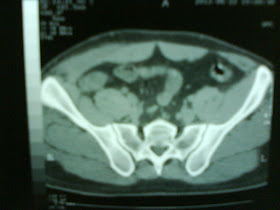

Rx-iMAGENES

Proyección anteroposterior y

lateral de codo derecho en el que se muestra perdida de congruencia articular

posterolateral.